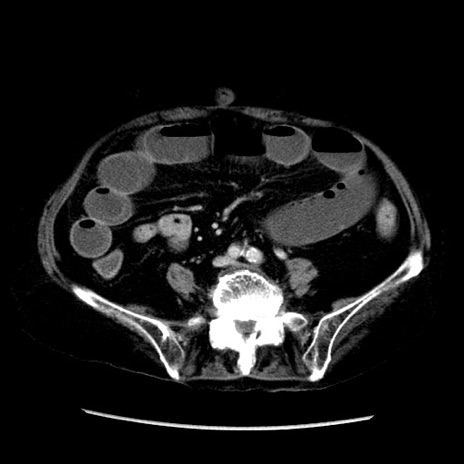

症例14(横断像)

【症例】 90歳代女性

【主訴】 腹痛・嘔吐

【現病歴】今朝から左側腹部痛を認めた。 経過観察していたが、嘔吐を認めたため来院。

【既往歴】 子宮癌術後

【身体所見】 意識清明、BP 127/54mmHg、P 98bpm Sp02 95%(RA)、BT 35.8°C、腹部平坦・軟腸ぜん動音聴取良好、右下腹部圧痛(+) 反跳痛なし

【データ】WBC 9800、CRP 0.46